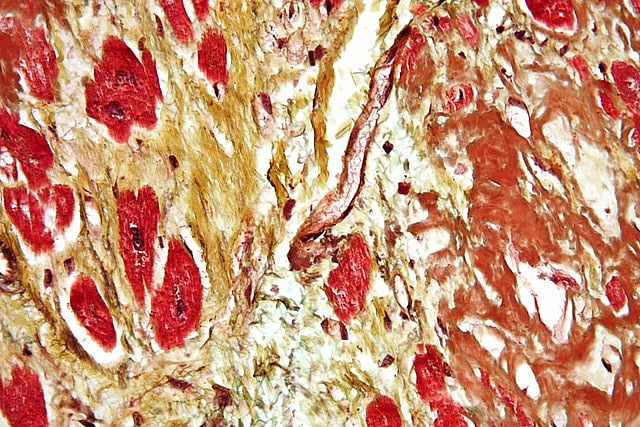

Cardiovascular diseases (CVDs) remain one of the leading causes of morbidity and mortality worldwide.  Wikimedia Commons